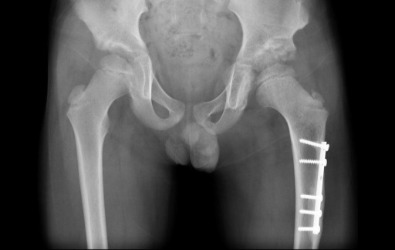

Μετ-εγχειρητικά

Οι ακτινογραφίες απεικονίζουν περιστατικά με αναπτυξιακή δυσπλασία στα ισχία, τα οποία παρουσιάστηκαν στην κλινική μας μετά την ηλικία των τριών ετών. Πραγματοποιήθηκε χειρουργική επέμβαση από τον Δρ. Ζένιο για ανάταξη των ισχίων με οστεοτομία λεκάνης και μηριαίου.